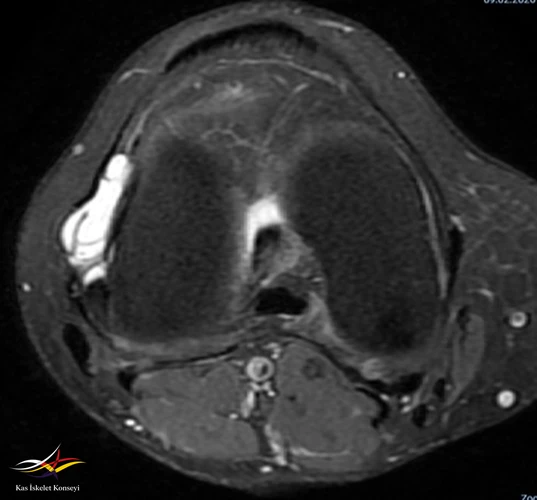

- Sağ diz MRG: Sağ diz ekleminde tibiofemoral ve patellofemoral eklem mesafeleri doğal olup, eklem yüzeyinde kartilaj yapı kalınlık ve sinyal intensiteleri tabiidir. Lateral menisküste longitudinal seyirli ve periferik uzanımlı rüptür ile lateral komşuluğunda LCL'yi deplase eden 22x32 mm boyutlu lobüle konturlu septalı parameniskal kist izlenmiştir. Medial menisküsün morfoloji ve sinyal intensite dağılımı doğal izlenmiş olup, patolojik sinyal intensite değişikliği saptanmamıştır. ACL, PCL'de hafif sprain mevcut olup, MCL, LCL tabiidir. Patellar ve quadriceps tendonların bütünlük ve sinyal intensiteleri tabiidir.

Resim 2. MRG aksiyal kesit.